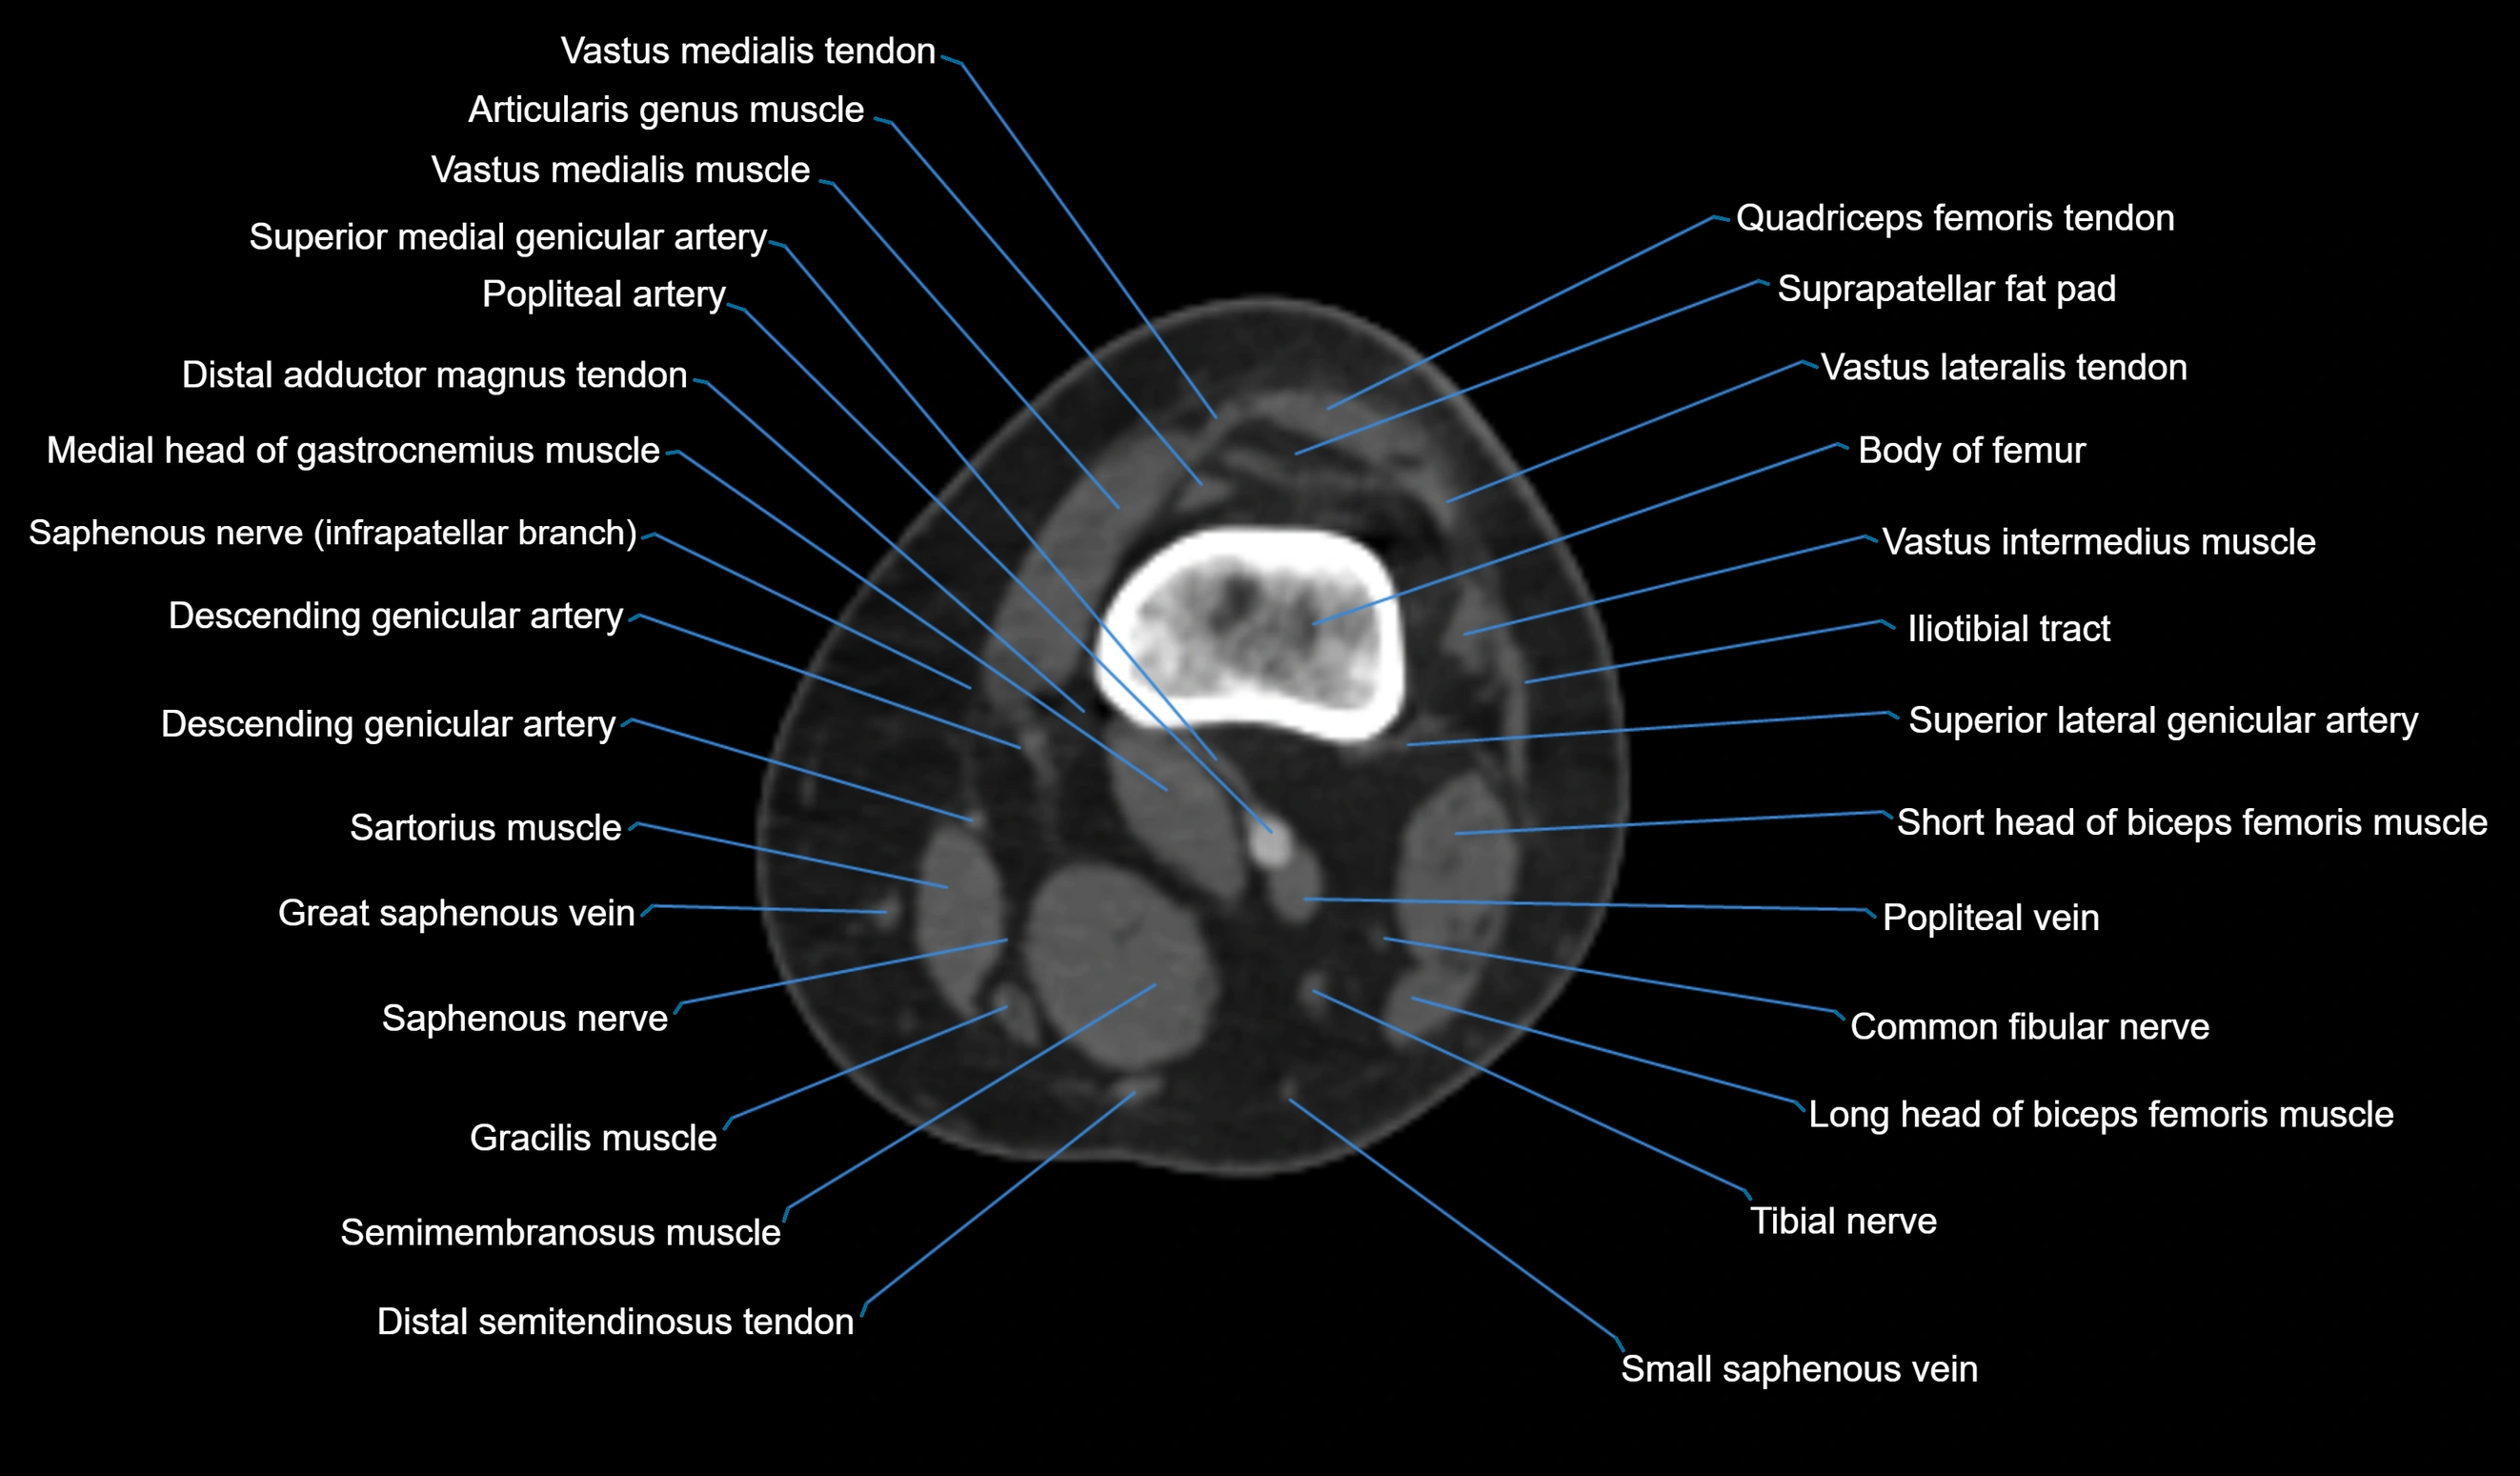

- Body of femur

- Common fibular nerve

- Descending genicular artery (Articular branches)

- Descending genicular artery (Saphenous branch)

- Distal adductor magnus tendon

- Distal quadriceps femoris tendon

- Distal vastus lateralis tendon

- Distal vastus medialis tendon

- Gracilis tendon (Distal)

- Lateral head of gastrocnemius muscle

- Medial head of gastrocnemius muscle

- Popliteal artery

- Popliteal vein

- Saphenous nerve

- Sartorius muscle

- Semimembranosus muscle

- Small saphenous vein

- Superior lateral genicular artery

- Superior medial genicular artery

- Suprapatellar fat pad

- Tibial nerve

- Vastus medialis muscle